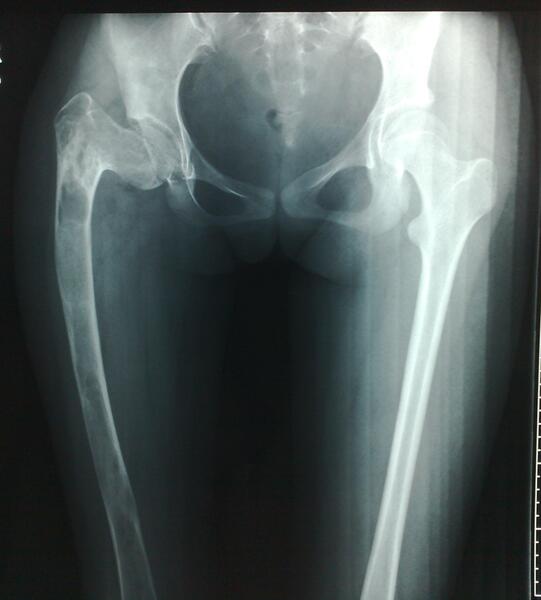

图1女性,18岁,术前肢体短缩9cm图2 术后力线纠正

图3 术后肢体等长